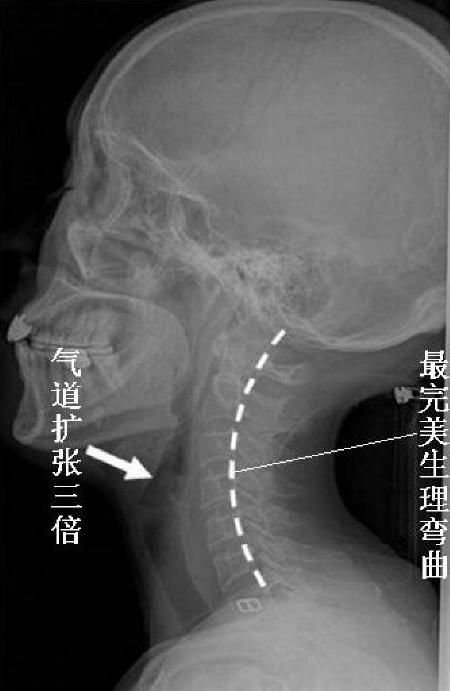

正常頸椎生理彎曲,可以使人呼吸通暢

從上面一組圖我們可以看出,頸椎正常的生理彎曲很重要。但現(xiàn)在,由于電腦的使用,很多人的頸椎都出現(xiàn)了不應(yīng)有的病變,頸曲度消失,甚至反張,會(huì)導(dǎo)致腦血出現(xiàn)障礙,引起包括頭暈、肩頸痛、手臂麻,以及頸心綜合癥等一系列問題,而昆叔正是由客戶的頸紋判定她的頸椎不好的。